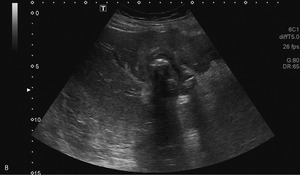

63-letnią kobietę przyjęto na oddział chirurgiczny z przewlekłymi bólami brzucha nasilającymi się w ostatnich 3 tygodniach. Od tygodnia obserwowano zażółcenie powłok, wymioty, odbarwienie stolca i brak łaknienia, co sugerowało żółtaczkę mechaniczną. W ciągu ostatnich 2 miesięcy masa ciała pacjentki zmniejszyła się o 8 kg. Na podstawie wcześniejszych badań USG, wykonanych 10 i 12 lat temu, rozpoznano u niej kamicę pęcherzyka żółciowego. Żółtaczkę potwierdzono w badaniach laboratoryjnych. Wykazano w nich także leukocytozę oraz podwyższone stężenie dimera D i CRP. W wykonanym przy przyjęciu badaniu USG zaobserwowano liczne złogi w pęcherzyku żółciowym i pogrubienie jego ściany z nieregularnym hiperechogenicznym naciekiem w sąsiadującym miąższu wątroby. Stwierdzono także poszerzenie dróg żółciowych wewnątrzwątrobowych w obrębie prawego płata oraz obecność niewielkiej ilości wolnego płynu w jamie otrzewnej (ryc. 1A, B). W dnie pęcherzyka uwidoczniono silne echo zlokalizowane w zarysie ściany narządu (ryc. 1C).

Wszystkie przedstawione warianty rozpoznania są prawdopodobne. Obraz USG z ryciny 1C sugeruje obecność złogu poza obrysem zmienionego zapalnie pęcherzyka żółciowego (rozpoznanie kamicy jest oczywiste na podstawie wcześniejszych obrazów). Bezdyskusyjne jest także rozpoznanie rozległego nacieku, prawdopodobnie zapalnego, w ścianie i w sąsiedztwie pęcherzyka. Fakt ten mocno uprawdopodabnia wytworzenie odleżyny w dnie pęcherzyka, perforacja jego ściany i migracja złogu do jamy otrzewnej.